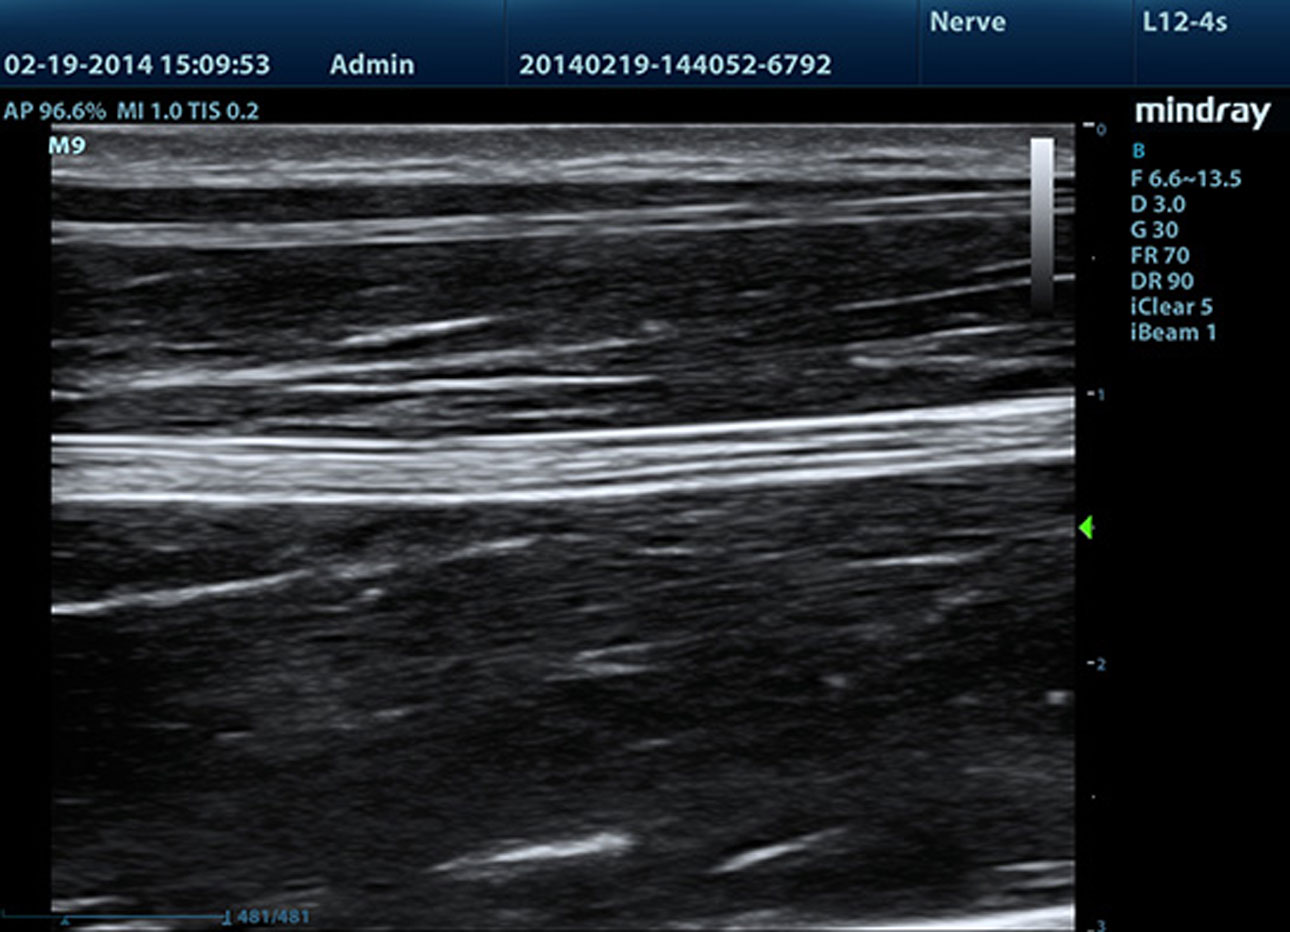

iNeedle?(Needle Enhancement Visualization)

Advanced needle visualization allows the needle increased visibility even during steep-angled procedures, while maintaining superior image quality. Improved confirmation of needle location in tissue minimizes harm to surrounding tissue.